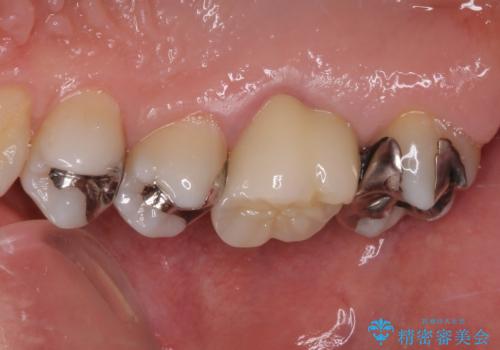

根管治療後には痛みが引き、半年後のレントゲンからは根尖部の病変が縮小している様子が分かりました。

咬んだときの感触も良好で、患者様には大変満足していただきました。